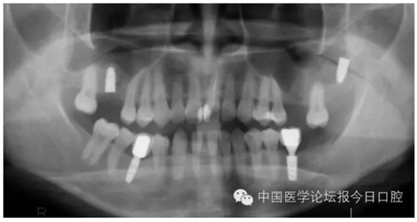

病例8 多顆種植體植入(圖10)

圖10

病例9 種植體進(jìn)入額竇腔內(nèi)(圖11)

圖11

?、芊N植體植入上頜竇或其他竇腔的情況較少見,但可能在患者為Ⅳ類骨或骨量少時(shí)發(fā)生,5~6mm骨量時(shí)也可能發(fā)生(如圖11所示)。